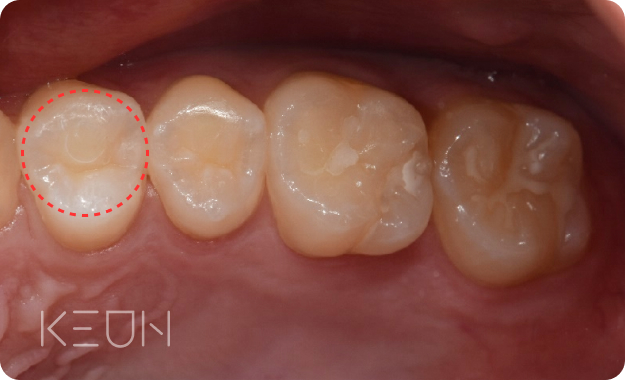

인레이

충치 범위가 크고 눈에 띄는 부위의 치료에 적합

- Before

로그인 후 확인 하실 수 있습니다!- After